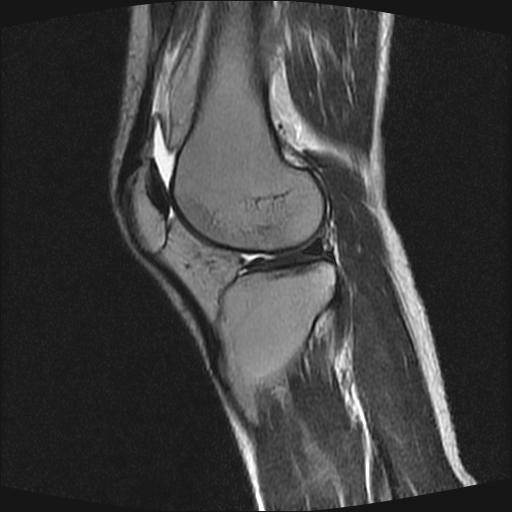

40岁男性,右膝关节外伤,x光平片示,髁间隆突撕脱骨折。

1、前交叉韧带撕裂;

2、外侧半月板后角撕裂;

3、关节腔积液。

前交叉韧带撕裂,关节腔积液.

半月板1-2级损伤   前交叉韧带撕裂伤   关节腔少量积液  诸骨未见新鲜外伤性改变

髁间隆突撕脱骨折;内侧副韧带损伤。

内侧副韧带撕裂及关节腔积液是肯定的,但是前交叉撕裂确定吗?会不会有容积效应的因素,因为前一张前交叉显示清楚,连续性良好,且较光滑。请问楼主有关节镜支持吗?我们医院也经常有这样的患者,但苦于没有关节镜,而无法对照、证实(除非完全断裂),出现了不同的诊断结果只能毫无意义的争论。

1、前交叉韧、内侧副韧带撕裂;

3、关节腔积液。4、髁间脊撕脱骨折。